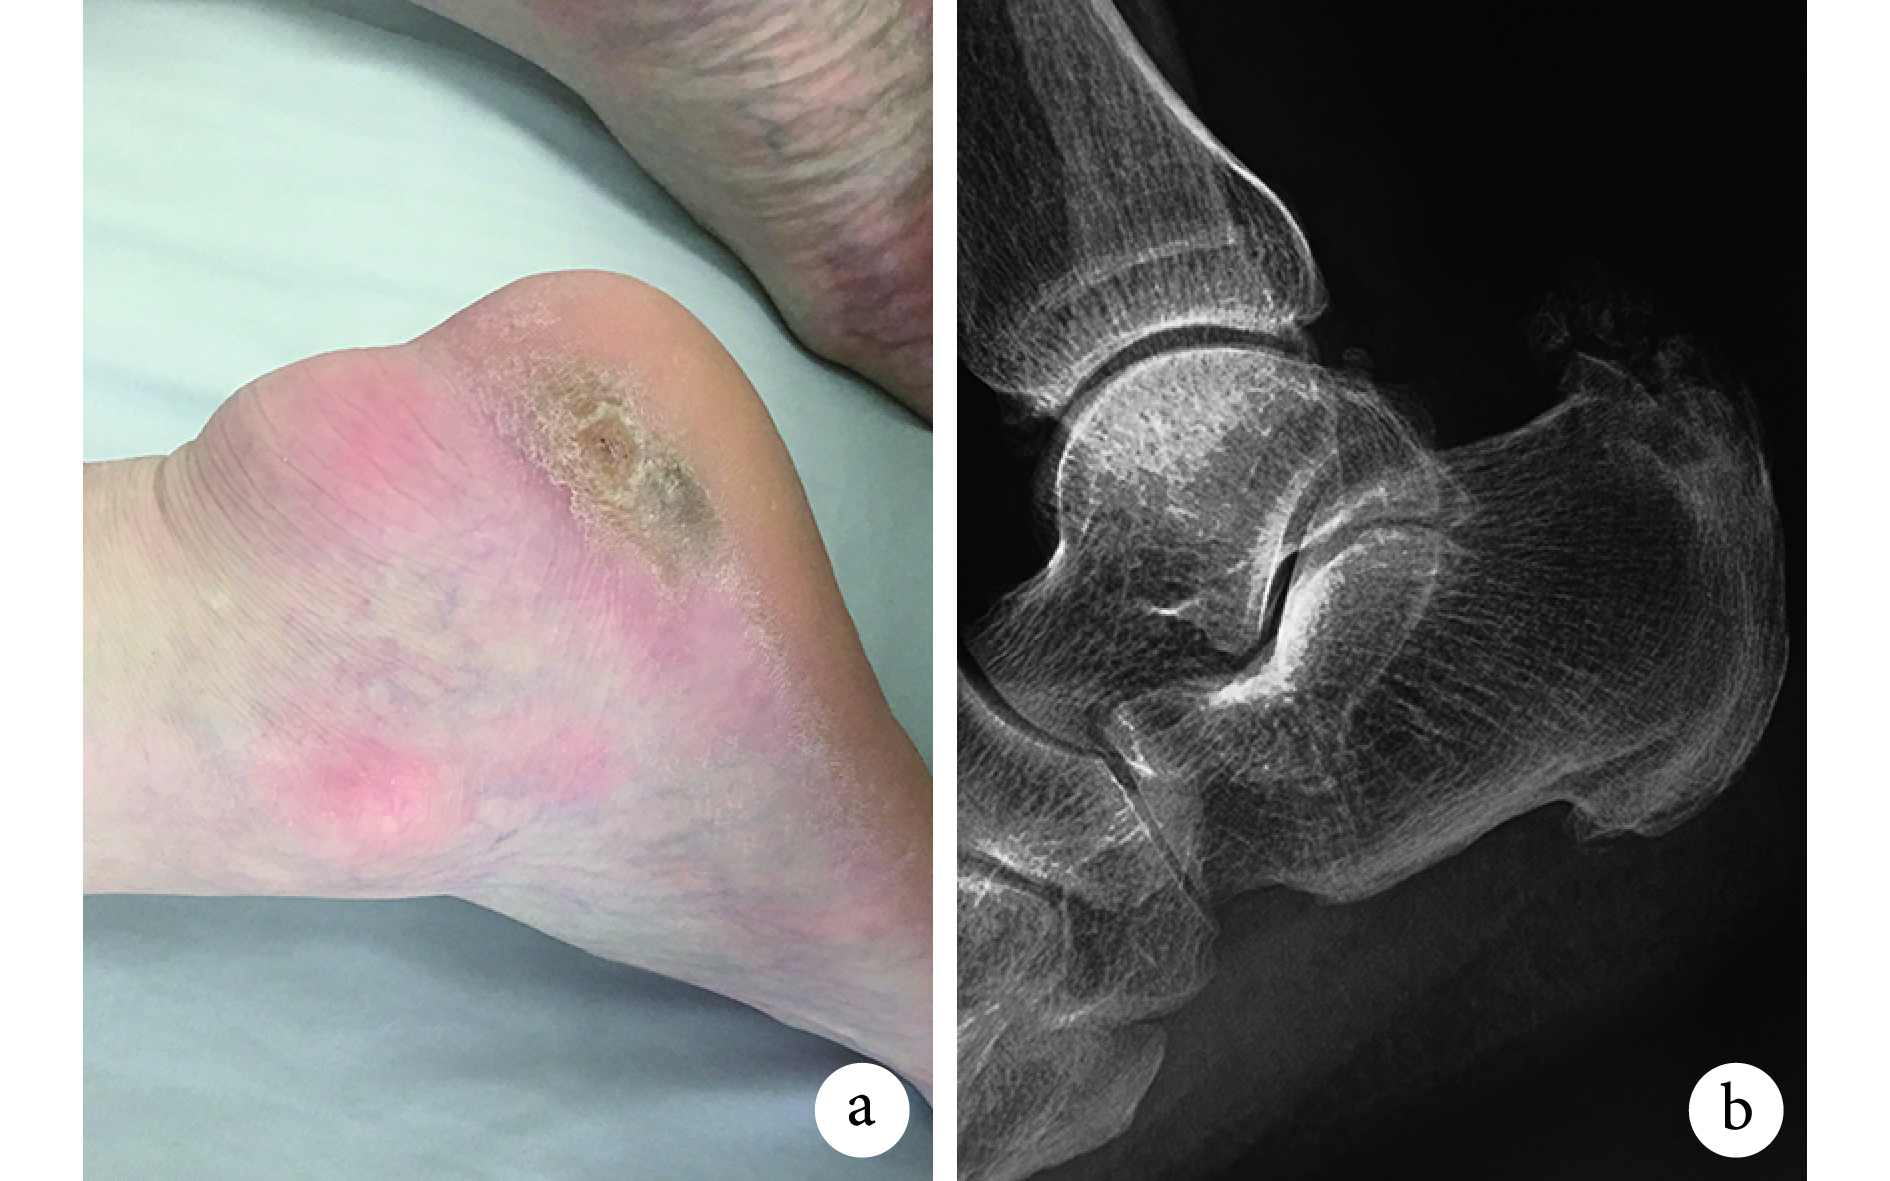

Haglund 綜合征是通過跟骨后上方的紅腫和疼痛診斷的,部位通常偏外側[23]。診斷依據主要包括:① 持續性跟骨后上方偏外側的腫痛,主被動踝背伸和跖屈時疼痛加重(跟骨撞擊試驗陽性);② 跟骨后上方偏外側質硬突起,局部壓痛,但早期外觀可無改變(圖 1a);③ 跟骨側位 X 線片示跟骨后上方骨性突起,甚至有骨贅形成(圖 1b);④ 符合以下影像學測量診斷指標。

a. 外觀;b. 側位 X 線片

Figure1. Clinical photograph and X-ray film of the Haglund malformationa. Clinical photogragh; b. Lateral X-ray film